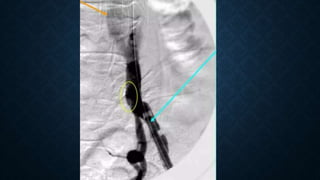

• The stent graft is flushed with heparinized solution

and advanced into the proximal neck. A repeat

angiogram is commonly performed to reconfirm the

positioning of the device within the aorta and the

landing zone

• Prior to device deployment, different manufacturers of TEVAR devices recommend the induction of transient

cardiac arrest or a significant decrease in blood pressure to obtain precise deployment of the device, avoiding

migration secondary to forward arterial blood flow.

• During deployment, another option is to place a transfemoral venous pacing wire, and rapid pacing can be done to

prevent ejection.

• The ventilator is stopped shortly for device deployment in to eliminate motion artifact

• After the deployment, the stent graft is ballooned to decrease

the possibility of Endoleaks

• A completion angiogram is performed to confirm lack of

gross Endoleak